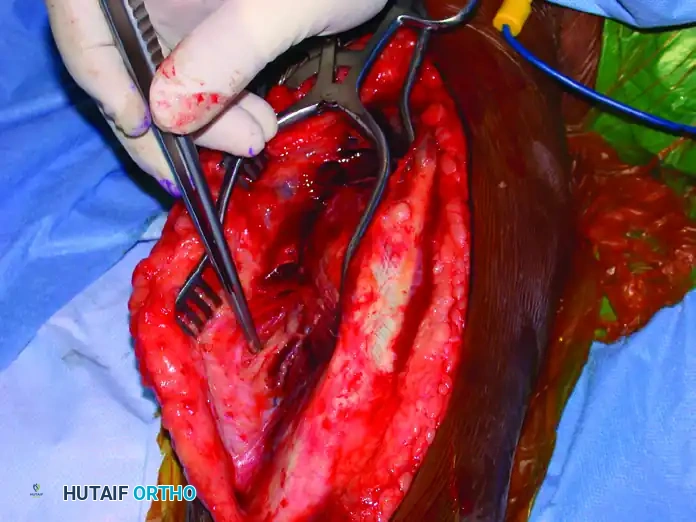

Deep Dissection and Fracture Exposure

- With the radial nerve protected (often using a vessel loop, though care must be taken not to apply excessive traction), incise the triceps off the periosteum to expose the humeral shaft.

- Biomechanical Imperative: Preserve as much of the periosteum as possible. Excessive periosteal stripping devascularizes the fracture fragments, significantly increasing the risk of nonunion.

Fracture Reduction and Provisional Fixation

- Place a single bone clamp (e.g., a pointed reduction forceps or Verbrugge clamp) on the proximal and distal fragments. Ensure these clamps are placed far away from the fracture site to control the fragments and simultaneously reflect the triceps.